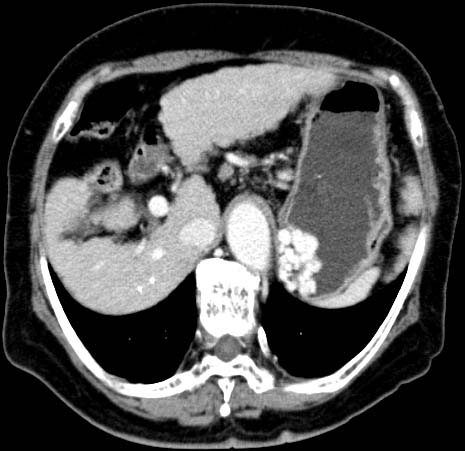

Gastric varix

3mmx4, Pitch 3.5, 273mm, 13 seconds, 150mAs

Oblique MPR